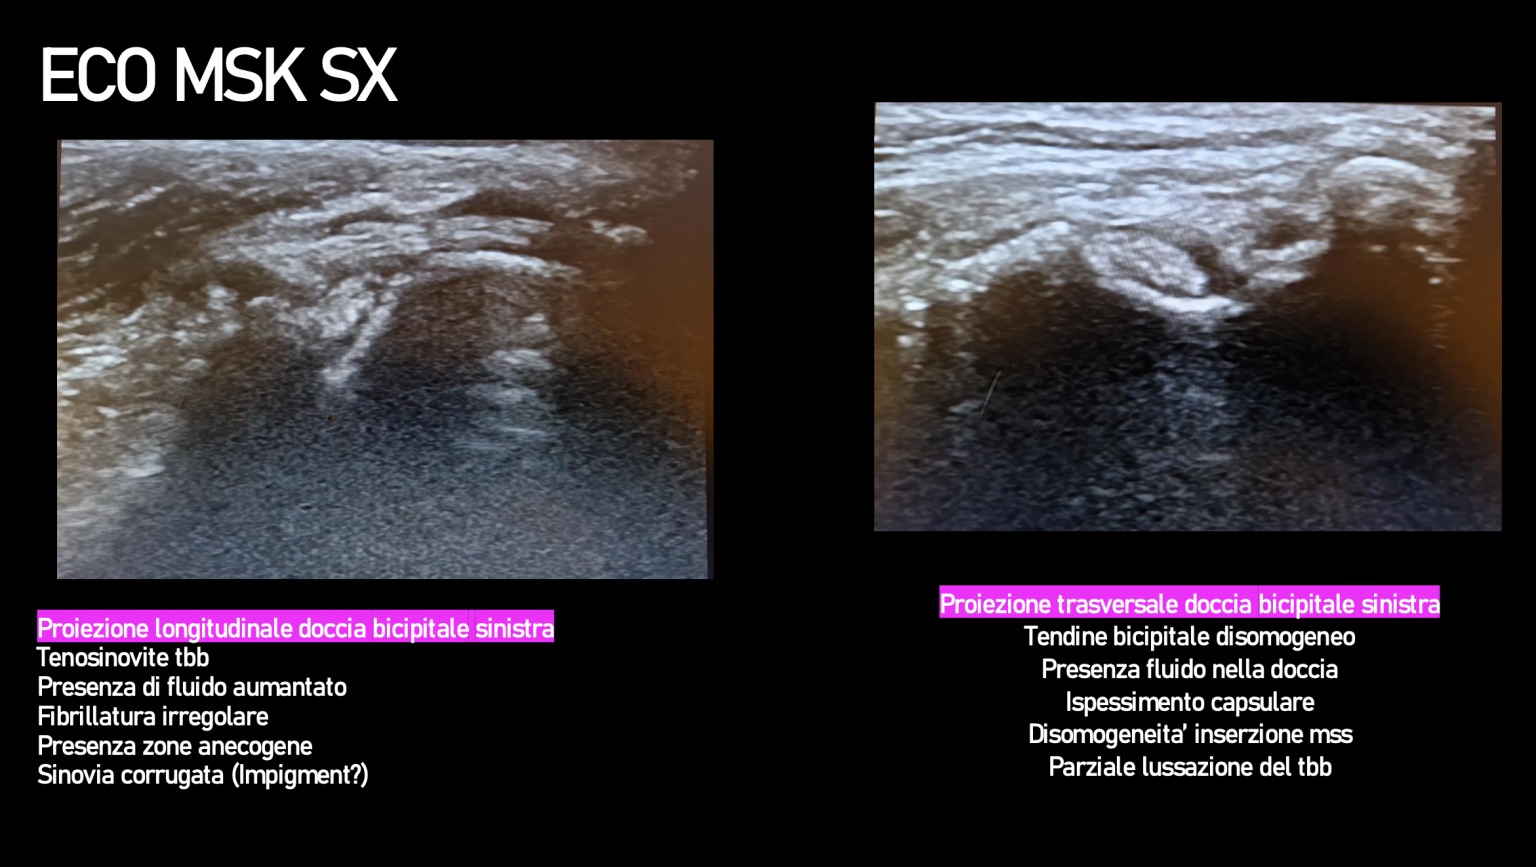

La locomotion est objectivée avec les différents paramètres mesurés à l’aide de l’outil Tendiboots™ Canine. Des examens radiographiques et échographiques ont également été effectués sur Kara.

![]() |